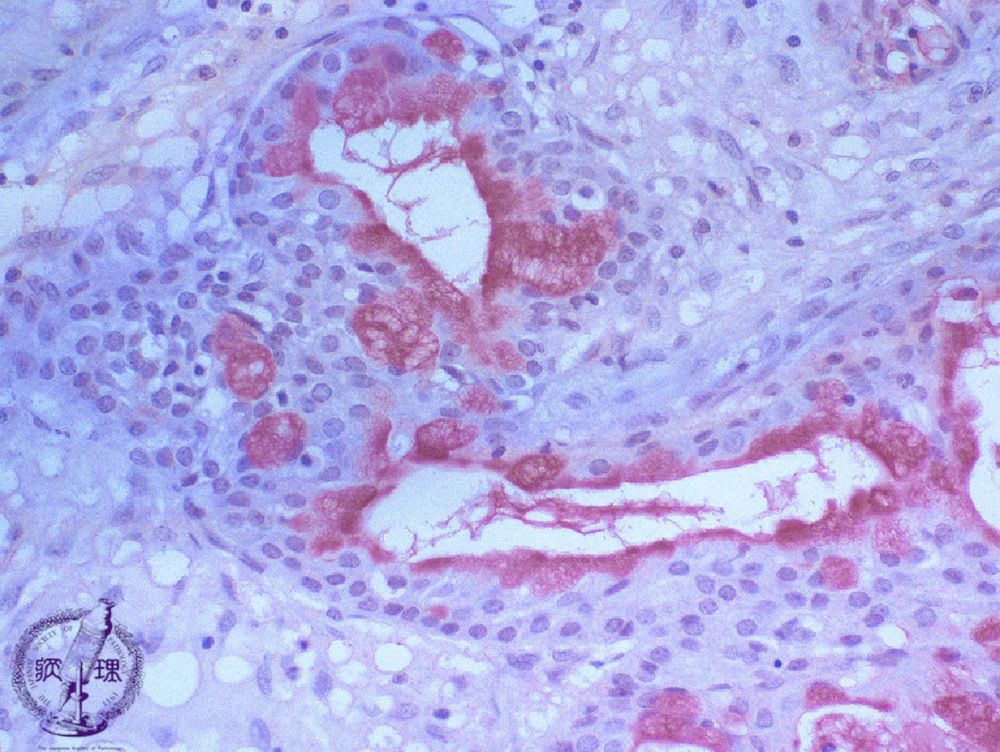

Microscopic finding (Mucicarmine stain, high-power view):Mucus producing cells and lumenal contents are stained red by mucicarmine stain (stain for epithelial mucin).

Click the image to see the enlarged image.

• There is no guidance by arrows.